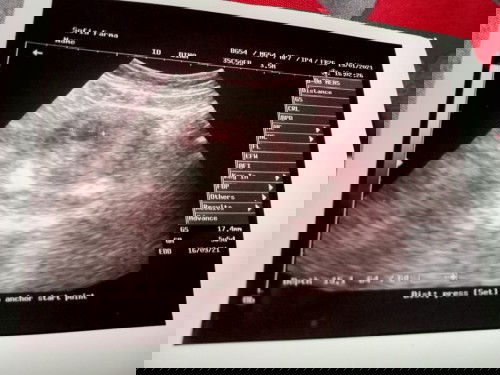

Bun, aku usg bru 5w tapi janin nya msh blum kelihatan & kantong janin nya msh di atas, normal kh bun

msh normal kok. sy jg USG TV 5w msh berupa kantung ukuran 0,5cm. selama letaknya d dlm rahim masih aman, bisa kontrol ulang sesuai dgn rekomendasi dokternya